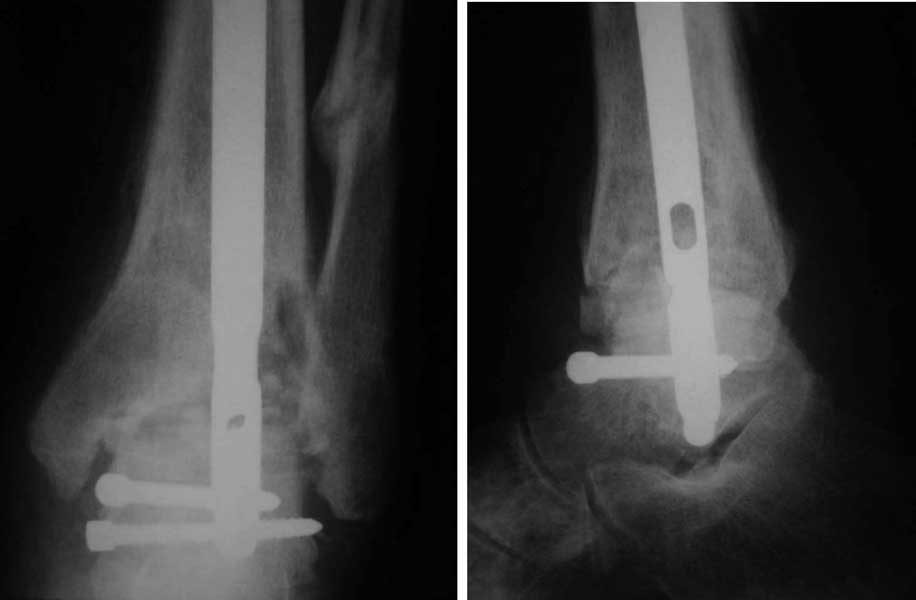

Интересный случай.  Допускаю, что состояние мягких тканей приемлемое. Цель  лечения должна  заключаться, как мне кажется,  в ликвидации ложного сустава и достижении артродеза голеностопного сустава. Впрочем, это две взаимосвязанные задачи. Мы бы оперировали следующим образом. Остеотомия малоберцовой кости на вершине деформации. Передне-медиальным  доступом артротомия голеностопного сустава, резекция суставных поверхностей с отломков большеберцовой и таранной костей, удаление рубцов между отломками дистального эпиметафиза большеберцовой кости,  антеградный  стержень с  дистальным блокированием в таранной кости, костная пластика дефекта спонгиозным костным трансплантатом из крыла (возможно сразу из двух) подвздошной кости. Банальные артродезы голеностопного сустава мы обычно выполняем антеградным блокированным стержнем (см. вложенный файл), что позволяет сохранить подтаранный сустав, и нагружать ногу сразу после операции.

Имя     : ankle arthrodesis.jpg